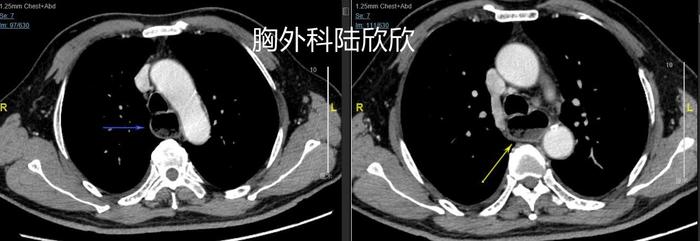

上图,脊柱前扩张的近端食管,扩张明显,内部有食物和粘液。肿瘤近端的食管明显扩张增粗。对于消化道肿瘤来说,只要是肿瘤引起的梗阻比较厉害,肿瘤近端的消化道管腔扩张就比较厉害。

上图,肿瘤周围的淋巴结,术后病理证实为转移淋巴结。只有这一个淋巴结发生转移。